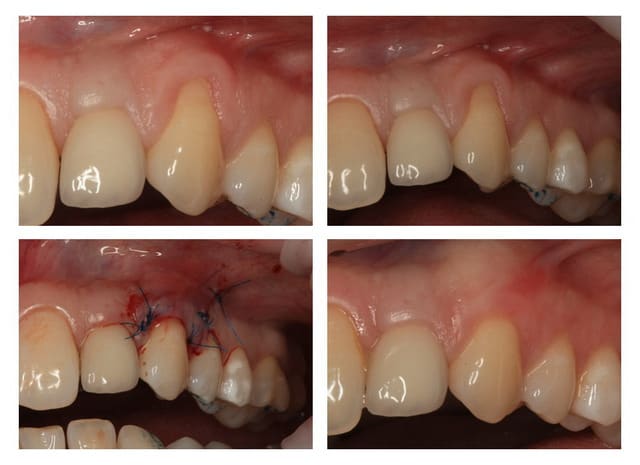

Comme on voit pas bcp de muco sur eugenol

P'tite 23 qui montrait trop de racine

Les 2 dernières photos sont à la dépose des fils (14 jours)

Il y a une "sling suture" pour la traction, le point collé au compo, est en plus, pour tester ;-)

Voici un cas similaire, encore une 23, perte de tissu plus grande, pas de point suspendu avec compo, seulement 2 "sling-suture".

Greffon tracté sous lambeau en mésial et distal comme le cas précédent avec sutures.

Pas d'incision vertical en mésial, surtout que la 22 est un implant, placé trop apical, donc risque de perdre papille distal de 22 +++. Petite incision vertical en distal de 23, pour tracter le lambeau.

Photo final à 4 mois, belle intégration du tissu je pense.